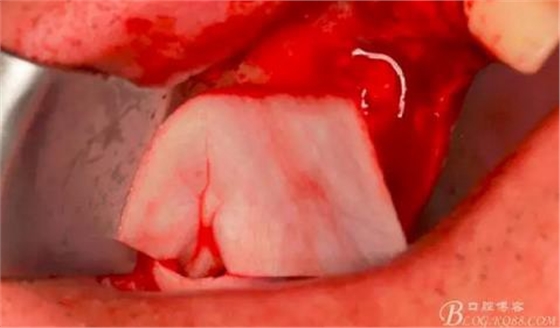

此時頰側(cè)竇膜與骨壁已經(jīng)分離,無需擔(dān)心開窗損傷竇膜。使用環(huán)切鉆以小洞口為中心開窗,轉(zhuǎn)速500轉(zhuǎn),為了保證安全,可以將種植機調(diào)成反轉(zhuǎn)模式,一樣有強大的切割效率。

因缺牙多,需要植骨的區(qū)域大,在遠中再環(huán)切一窗口。